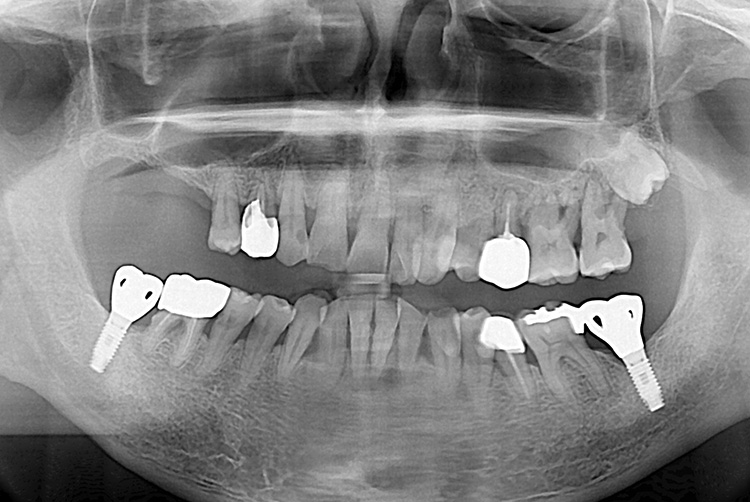

[임플란트] 임플란트

치료전 : 2016-05-04